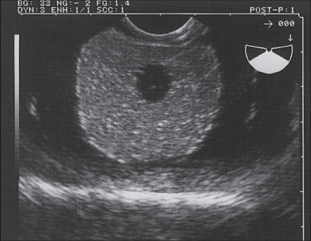

CIRS designed the Ultrasound Prostate Training Phantom as a multi-modality disposable phantom developed for practicing procedures that involve scanning the prostate with a rectal probe. There are three different models: Model 053S, 053L and 053L-EF.

The clear, acrylic container contains the prostate along with structures simulating the rectal wall, seminal vesicles and urethra. A 3 mm simulated perineal membrane enables various probes and surgical tools to be inserted into the prostate.

This phantom is an ideal training device for ultrasound guided cryosurgery, radioactive seed implantation, and needle biopsy.